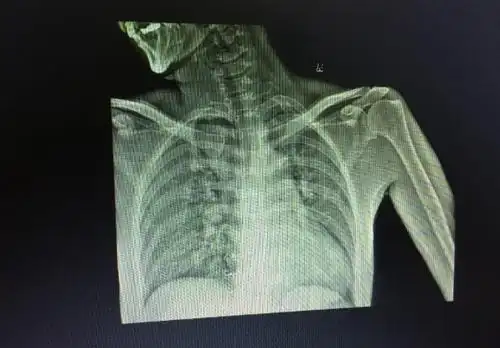

左侧肩胛骨骨折